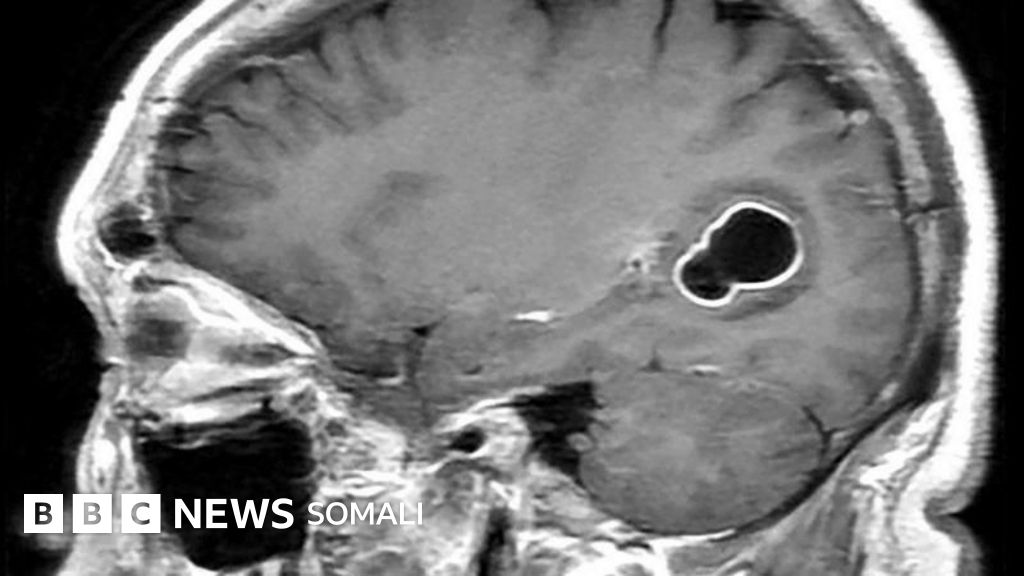

Dhakhaatiir u dhalatay dalka Maraykanka ayaa daaha ka qaaday in bukaan la ildarnaa xanuunka dhanjafka xooggan ee soo noqnoqda u uku sababay xanuunkan tirxi ama gooryaan ku dhex noolaa maskaxdiisa.

Dhakhaatiirtu markii ay samaynayeen baadhista raajada madaxa, waxay ogaadeen in maskaxdiisa ay ku jiraan fiixyo badan oo, sida ay markii dambe ku xaqiijiyeen daraasado ka dambeeyay, dhab ahaantii ah dirxi dhogor leh oo ku nool maskaxdiisa kaas oo ku sababay caabuq loo yaqaan ‘neurocysticercosis’.

Caabuqan waxaa keena dirxiga Taenia solium (T.solium), oo sidoo kale loo yaqaanno gooryaanka doofaarka.

Bukaanka waxaa la siiyey daawooyinka lagu dilo dirxiga iyo bararka wuxuuna sameeyay soo kabasho buuxda.